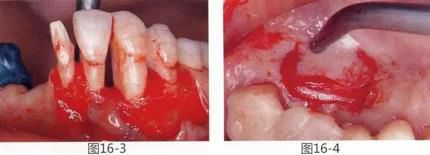

圖16-3  通過牙周外科將牙周袋去除,獲得附著齦,牙槽嵴增大。

圖16-4  從腭側(cè)采集結(jié)締組織瓣。